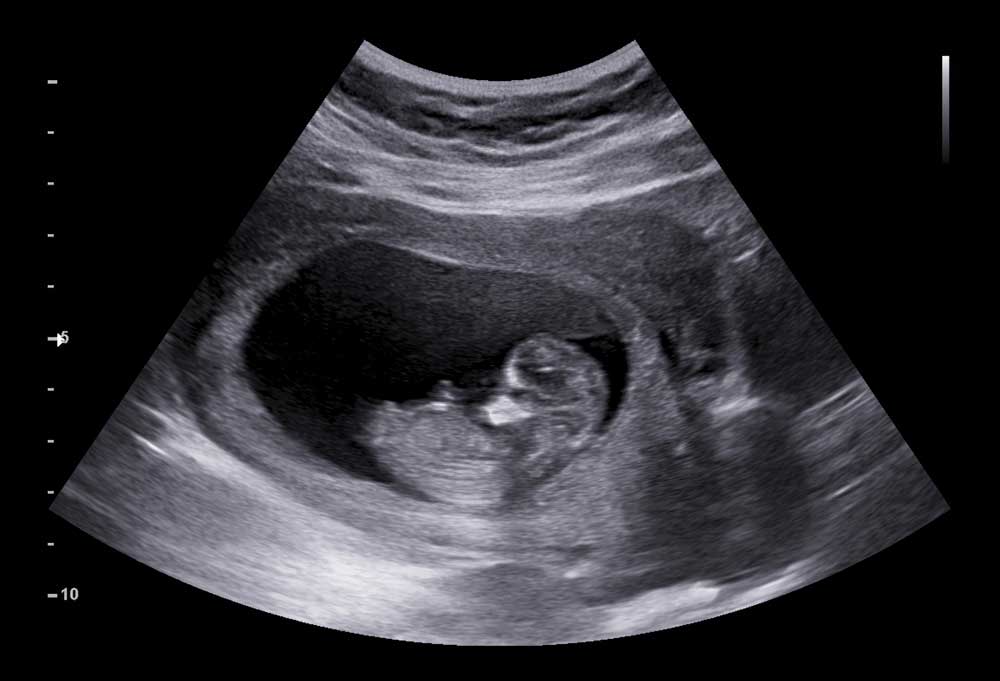

• Regularly monitor foetal growth, amniotic fluid, and placental function through ultrasounds.

• Besides the regular NT scan and Dual Marker to detect chromosomal abnormalities between the 11th and 14th week of pregnancy, you will be offered the more comprehensive Non Invasive Prenatal Testing ( NIPT) to rule out chromosomal problems in the foetus.